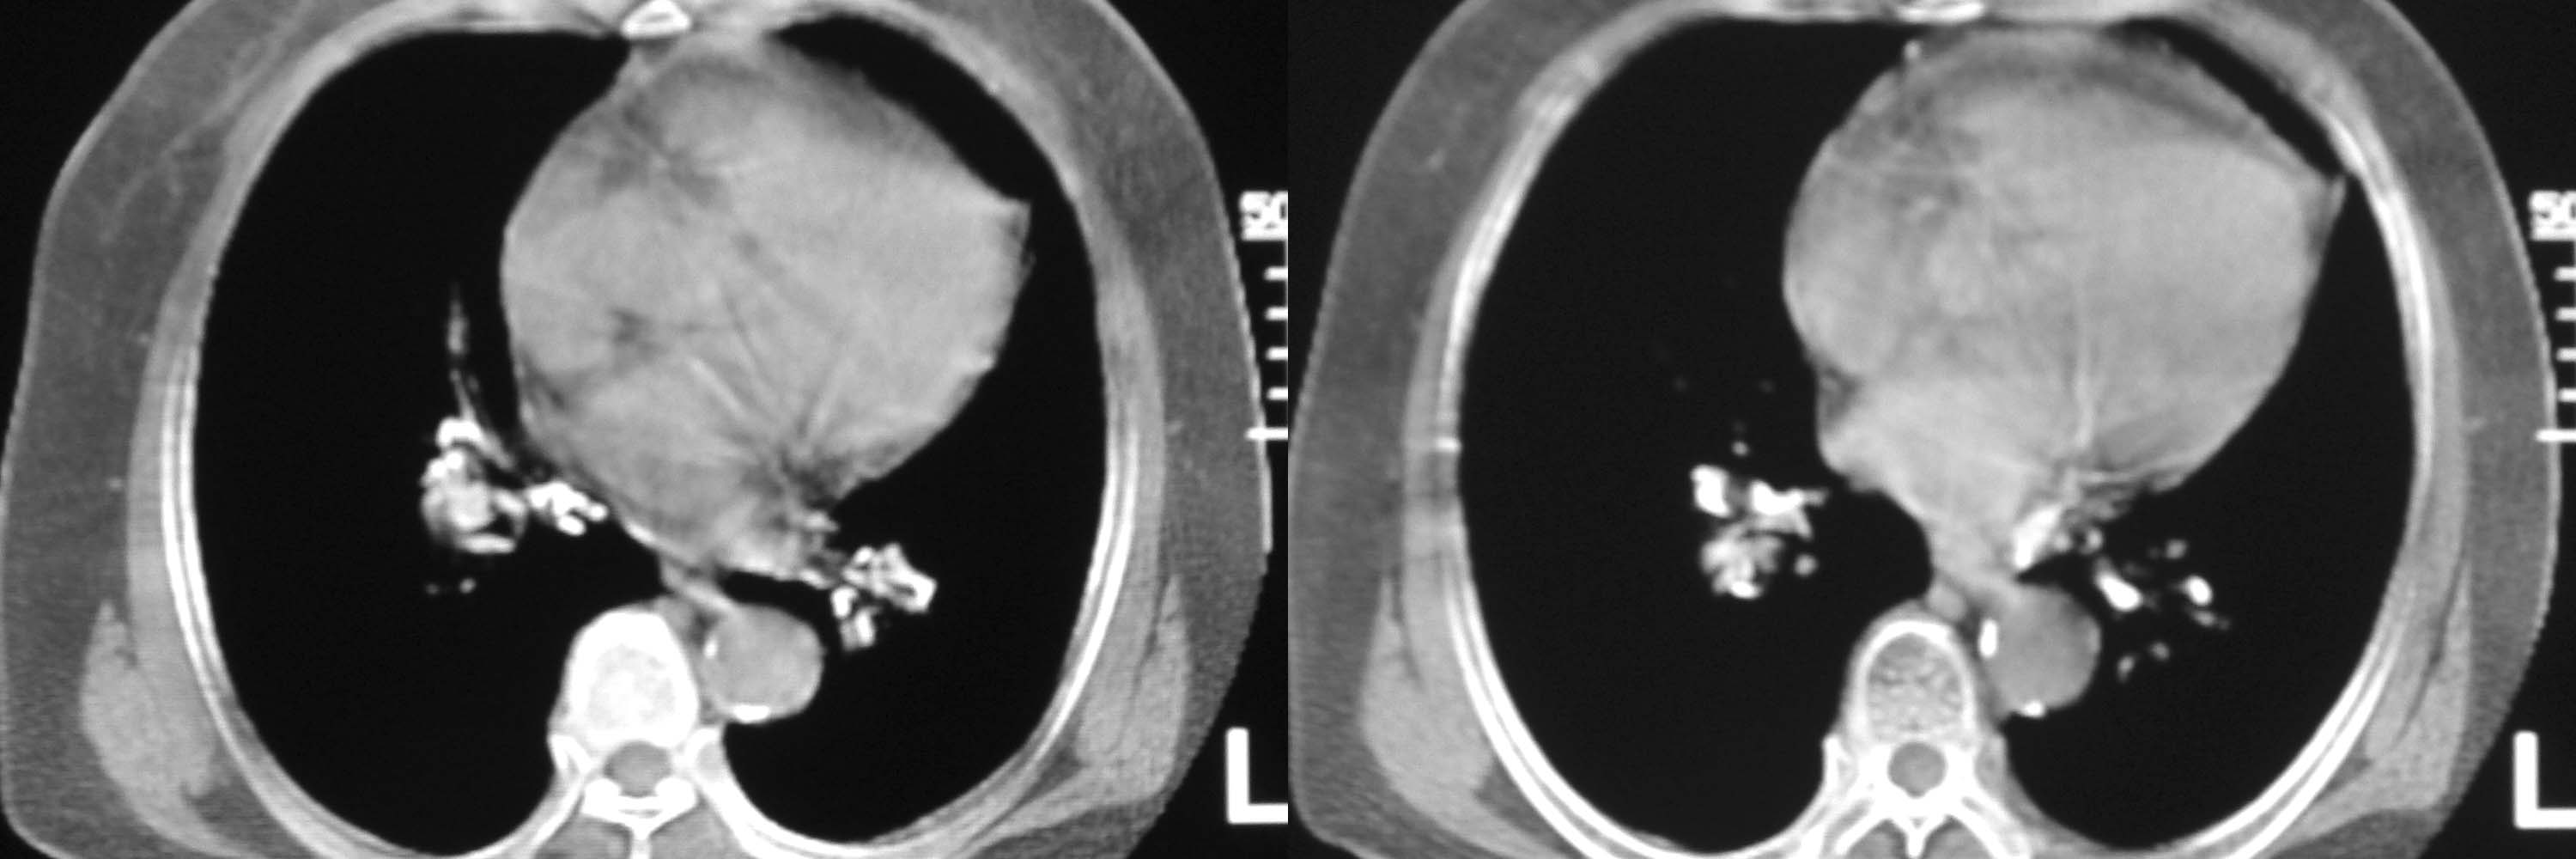

女78岁咳嗽咳痰无咳血平片报右上肺不张、慢支、肺气肿、请老师们帮忙看看,箭头所指是什么?是占位吗?有肺气肿吗?谢谢

箭头所指----多考虑-----右头臂静脉旁淋巴结钙化

可能是逾曲的头臂血管

可能是纡曲的头臂血管——支持。

箭头所指考虑血管影

箭头所指考虑血管影;纵隔内及双肺门区多发淋巴结钙化;不支持肺气肿。

箭头所指考虑血管影(头臂血管);纵隔内及双肺门区多发淋巴结钙化;不支持肺气肿。